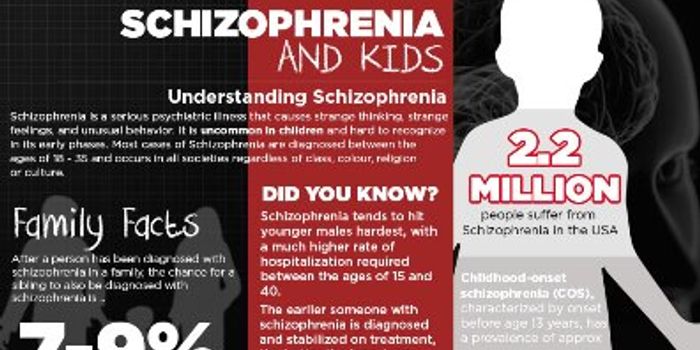

MAR 10, 2016InfographicsChildhood schizophrenia is a severe brain disorder which causes children to interpret reality abnormally. This type of m ...